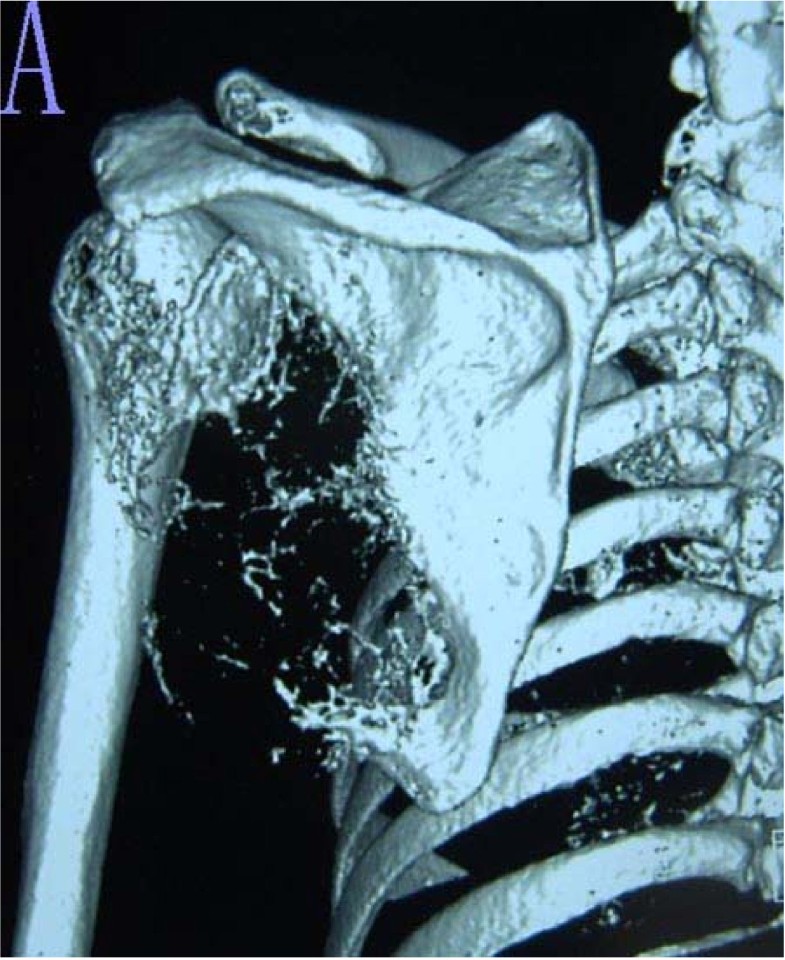

From jeccr.biomedcentral.com

Surgical technique and clinical results for scapular allograft Scapula Bone Cancer the most common primary malignant bone tumors include osteosarcoma, ewing's sarcoma (es), and. The pelvis, ribs, femur, and. chondrosarcoma is a malignant mesenchymal tumor originating from cartilage. tumors occurred most frequently in the body of the scapula. neoplasms of the s2 region include those that commonly develop at the ends of the bone (i.e.,. sarcomas. Scapula Bone Cancer.